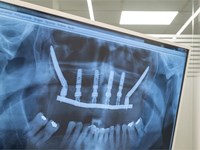

3 ventajas de los implantes dentales de carga inmediata

Perder una pieza dental no solo afecta a tu sonrisa: también pone en riesgo la salud del hueso que la sostenía. Y ya por culpa del paso del tiempo, esa estructura ósea puede debilitarse y reabsorberse, lo que complica futuros tratamientos. Por estos motivos, desde Titanium Clínica Dental & Estética, tus dentistas en Vigo, queremos hablarte de una solución eficaz, estética y muy cómoda: los implantes dentales de carga inmediata.